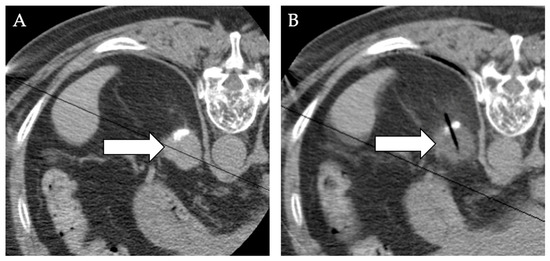

- Samadi, K.; Arellano, R.S. Ureteral protection during microwave ablation of renal cell carcinoma: Combined use of pyeloperfusion and hydrodissection. Diagn. Interv. Radiol. 2018, 24, 388–391. [Google Scholar] [CrossRef]

- Mauri, G.; Nicosia, L.; Varano, G.M.; Bonomo, G.; Della Vigna, P.; Monfardini, L.; Orsi, F. Tips and tricks for a safe and effective image-guided percutaneous renal tumour ablation. Insights Imaging 2017, 8, 357–363. [Google Scholar] [CrossRef] [Green Version]